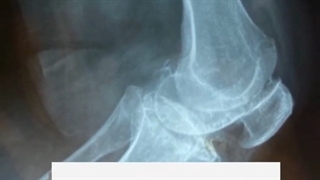

فیلم واقعی جراحی زانو